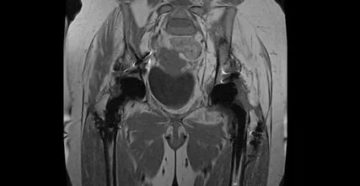

Свободная жидкость в малом тазу на УЗИ: признаки и симптомы, норма ли, что делать При…